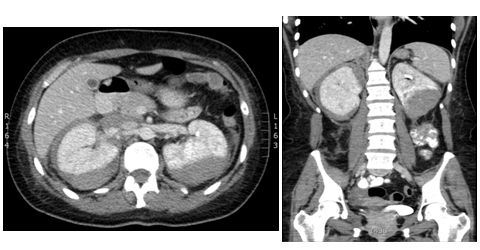

An unclear picture led to a CT pulmonary angiogram, which did not reveala pulmonary embolism but it was incidentally found that there were bilateral large renal haematomas (Figure 1). Subsequent blood tests revealed worsening renal function, inflammatory markers, and anaemia requiring blood transfusions. The patient was also found to be ANCA positive with a raised MPO titre of 134U/ml. A renal angiogram was performed and showed several renal artery aneurysms (Figure 2).

Figure 1 A) CT contrast abdomen, axial view showing bilateral capsular and subcapsular renal haematomas. B) CT abdomen sagittal view.